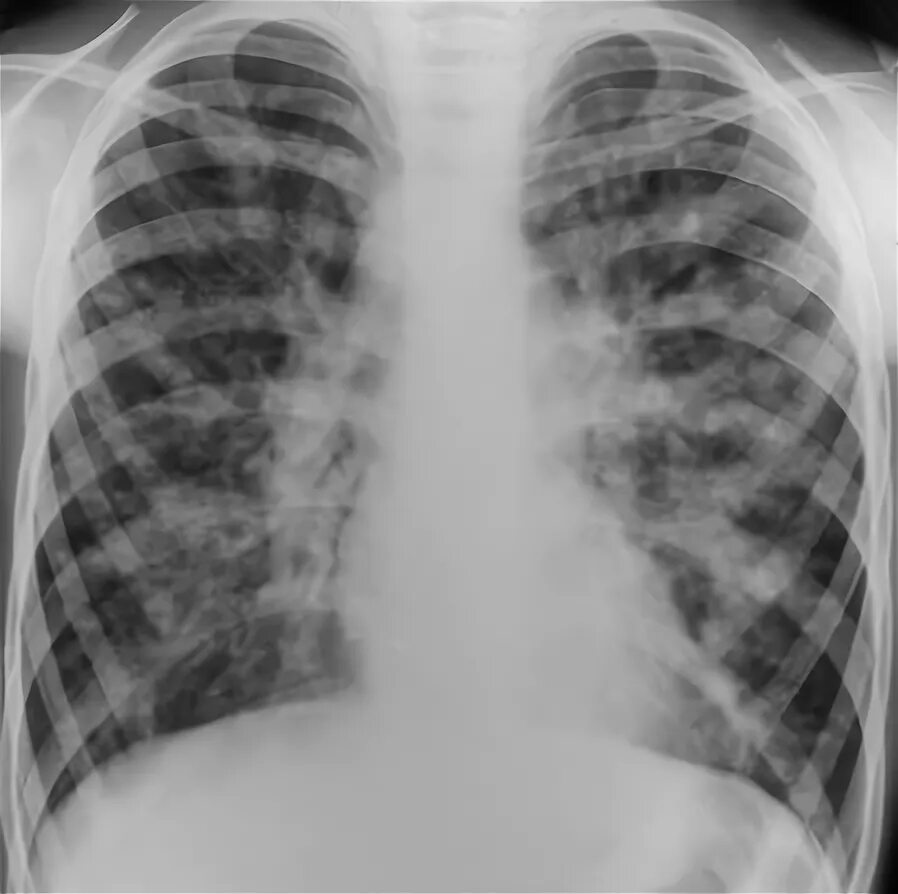

Диффузный эндобронхит